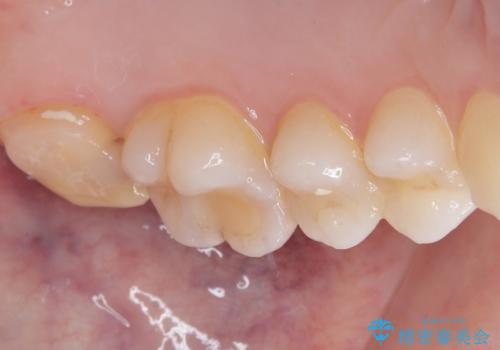

拡大鏡視野下で詰め物と虫歯の除去を行い、詰め物の範囲が大きかったためオールセラミッククラウンに適した形に整えました。

型どりはシリコーン印象材にて精密印象をしています。